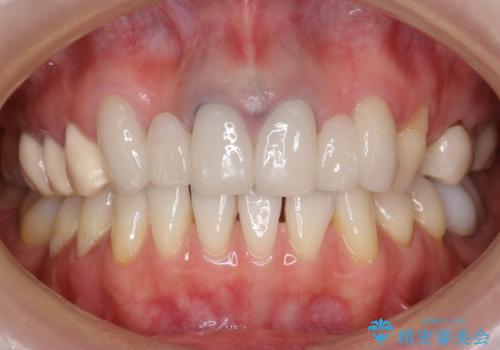

他院で仮歯まで入れたが違和感がある 40代女性

- 他院で仮歯まで入れたものの違和感があることを主訴に来院された患者様です。

違和感があると訴えたにも関わらずそのまま被せようとする他院に不安を感じ、通院をやめてしまったとのことでした。

丁寧にう蝕除去と再根管治療を行い症状の改善を確認したのち、セラミッククラウン及びセラミックインレーによる補綴を行いました。

まるで天然歯のような自然な見た目と咬み心地にご満足頂けました。

気にされていた違和感もなくなり、喜んで下さいました。

クラウンの種類:オールセラミッククラウン スタンダード